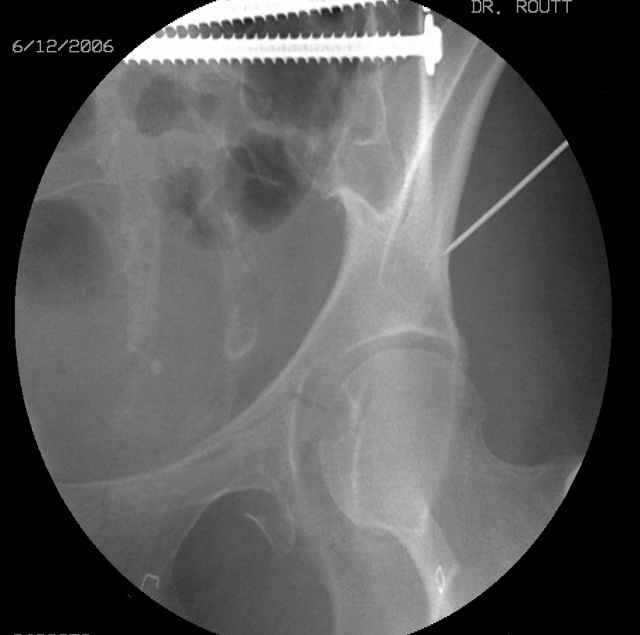

Here's a pic from the foot of the bed and you can see the clamp in the wound and the knee is extended so he must've had a tight rectus. The C-arm is rolled back to an obturator oblique image to reveal the anterior column...we put a slight outlet tilt to combine the images and give a better view of the anterior column...we can see the posterior column limb reduction in the wound, we can palpate the quadrilateral surface limb, and the image demonstrates the anterior column portion...you can adjust the tilt and rotation to image tangentially to the fracture plane if you'd like. We've inserted a 2mm K wire to site the starting point and aim/orientation for the drill and screw

Prone Imaging